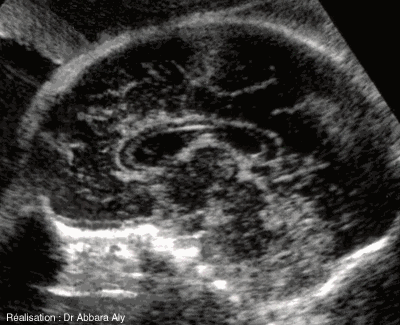

Face interne de l'hémisphère cérébral

et corps calleux

Atlas d'échographie